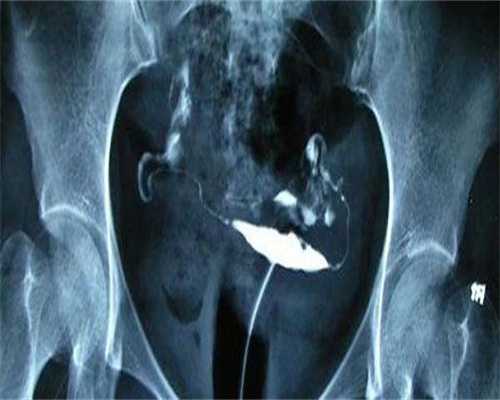

试管移植后注射黄体酮的效果是增加试管胚胎移植成功率的有效方法。试管移植是一种医学技术,用于帮助不孕不育患者实现母婴情结,它通过将体外受精的胚胎移植到女性的宫颈管内来实现。然而,由于试管移植的一些因素,移植成功率并不高。因此研究人员开发了一种新的疗法,即在试管移植后注射黄体酮,以提高移植成功率。

黄体酮是一种天然的激素,存在于卵巢中,其主要作用是促进卵巢发育,并促进排卵的过程。在试管移植中,当胚胎移植到女性的宫颈管内后,黄体酮能够帮助胚胎更好地适应新的环境,从而提高移植成功率。此外黄体酮还能够促进血液循环,有助于改善宫颈管的血液供应,进而提高胚胎的植入率。在注射黄体酮治疗过程中,需要首先确定患者的基础激素水平,然后根据具体情况进行不同剂量的黄体酮治疗,以提高植入率。黄体酮治疗一般需要一周左右,每次注射的剂量要根据患者的激素水平进行调整,以确保注射的安全性和有效性。